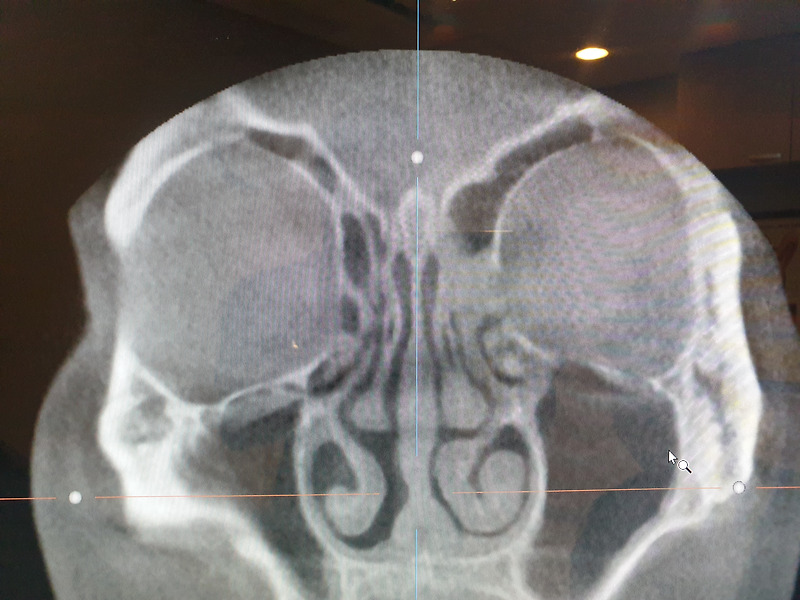

프리다이빙 부비동 통증

프리다이빙 중에 부비동 통증을 느꼈다. 송곳처럼 뾰족한 걸로 미간 쪽을 찌르는 통증 이었다. 다이빙 하면서 느꼈던 이퀄 이 안돼서 오는 고막 통증이랑은 다른 통증 이었다. 만성 비염을 가지